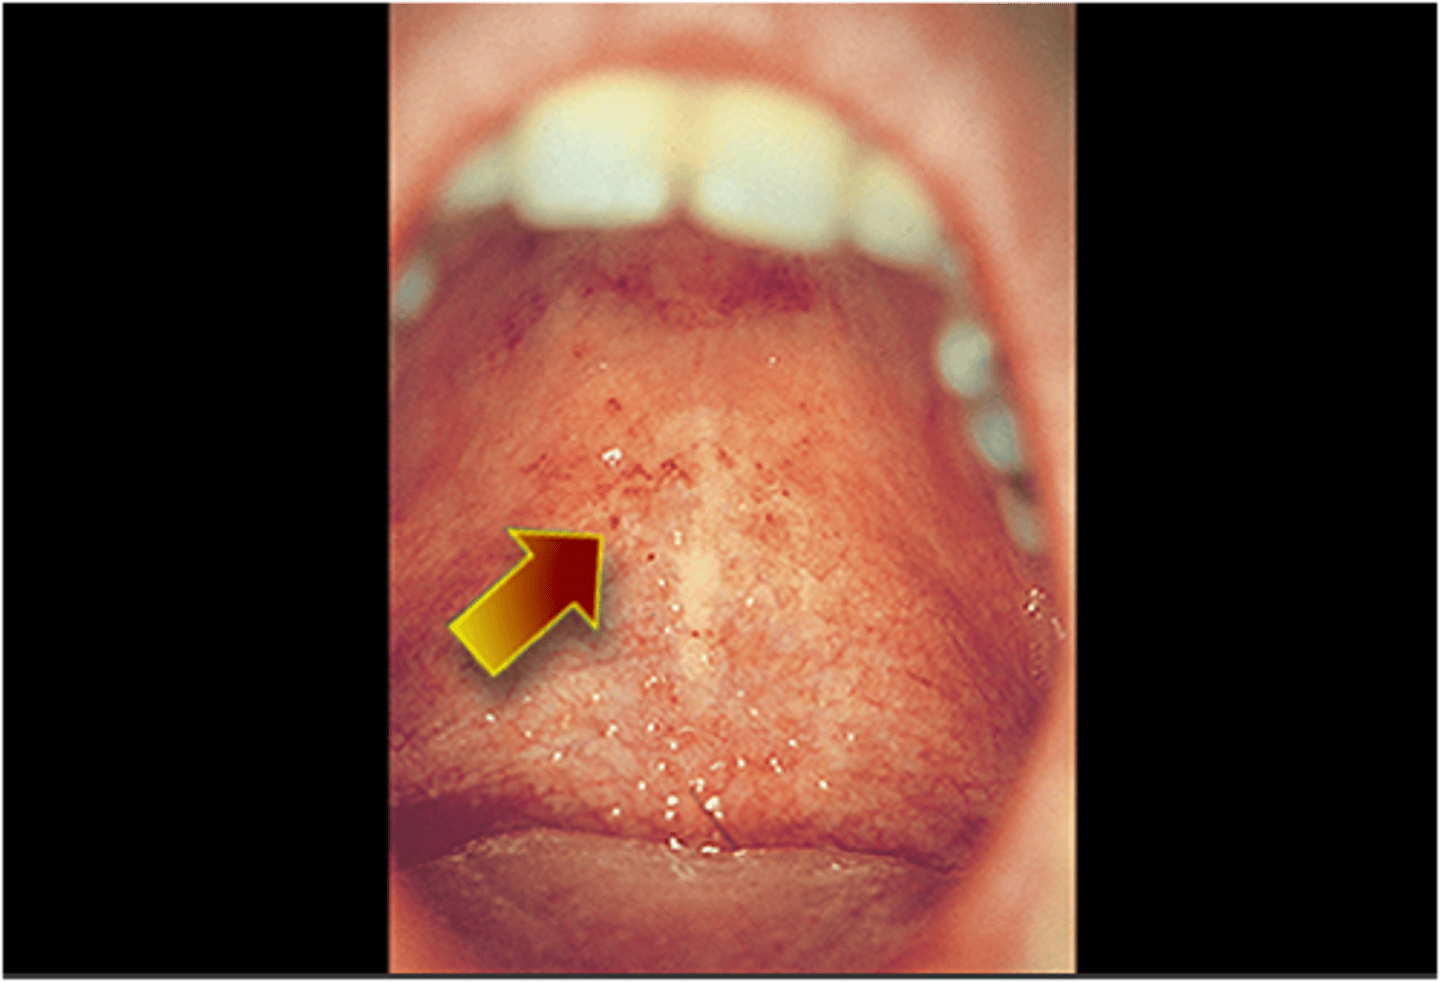

What are Forchheimer spots?

Forchheimer spots are small, red petechiae that appear on the soft palate and uvula during the prodromal phase of rubella (German measles). They are not pathognomonic but can help differentiate rubella from other viral exanthems